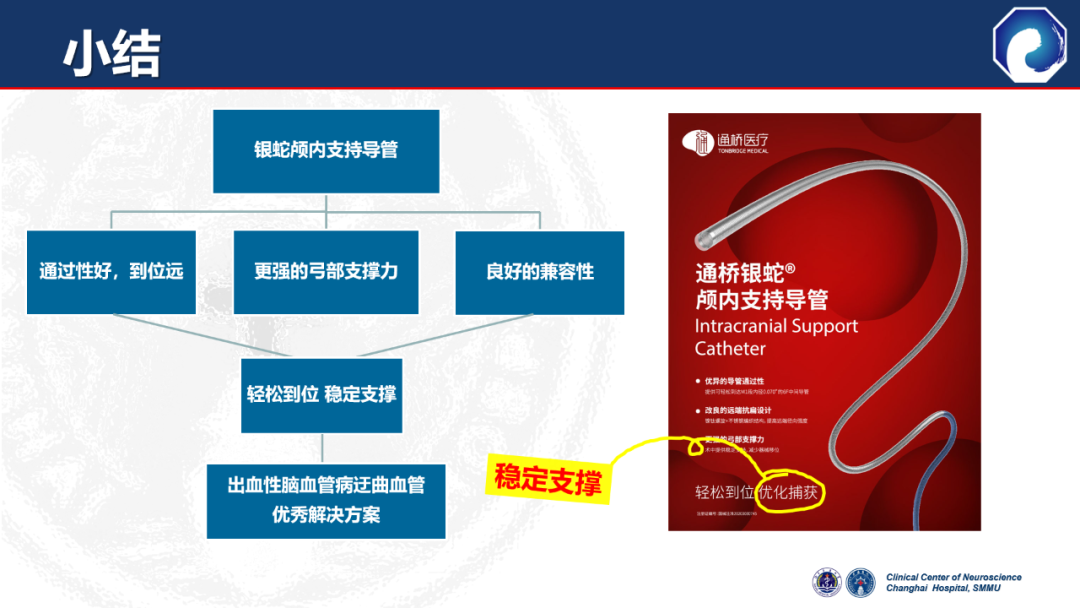

国产新一代远端通路导引导管:通桥银蛇®DA

7种材料的组合带来了更优的通过性与近端支撑力

与竞品DA相比,弓部和近端支撑力更强

40°头端预塑形,主动脉弓超选更容易。0.071大内腔设计,可以兼容多种器械

105cm长度设计,器械出头更容易

通桥医疗银蛇®DA在迂曲血管中也能实现高到位

通桥医疗银蛇®DA设计特点

通桥医疗银蛇®DA导引导管:

远到位(可以到达海绵窦段),强支撑。

多直接超选、无需长鞘,减少近端支撑需求。

0.071大内腔设计,满足动脉瘤多种治疗需求。

抗打折性可以进一步提升,减少、缓慢扭转,附加支撑有利于改善。